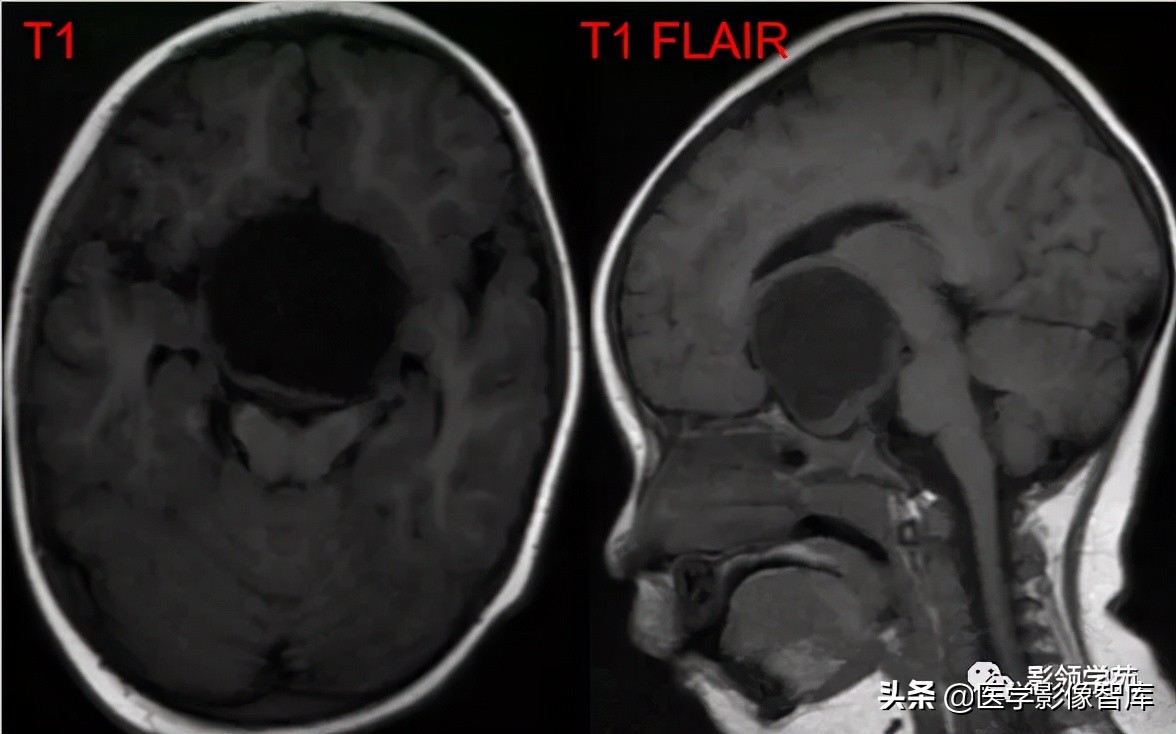

女 72岁,发现糖尿病3年余

鞍上区见一团块状稍高密度影,边界尚清,密度均匀。

鞍上右上方见一类椭圆形流空影。

病灶明显强化(瘤内血栓未强化),边界清楚,与右侧颈内动脉海绵段分界不清。垂体大小、形态未见异常。